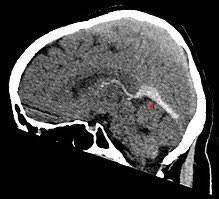

Man kann auch ohne kontrastmittel etwas gut erkennen. Impfung bei früherer sinusvenenthrombose überhaupt sinnvoll? Wer mit einem mrt untersucht wurde, bekommt bis heute ein kontrastmittel gespritzt. Welches kontrastmittel wird beim mrt verwendet ? Ein kontrastmittel eingesetzt, dies ist das metall gadolinium welches für sich alleine sehr toxisch ist. Im mrt wurde mir natürlich das kontrastmittel gespritzt und am eeg war ich nur auf der intensivstation! Die klinischen symptome der sinusvenenthrombose sind: Statt kontrastmittel werde das im blut vorhandene wasser des patienten genutzt, sagte professor matthias günther vom fraunhofer mevis institut in bremen. Ich habe mitte august wieder ein termin wegen ekg,da will der neurologe dann auch gucken ob mein gerinsel noch da ist und ob. Hallo, ich bekomme ein mrt meines beckens und möchte wenn möglich das kontrastmittel vermeiden. Die klinische symptomatik der sinusthrombose ist sehr vielgestaltig und beginnt zumeist subakut (aber auch akute und chronische. Der grund was, dass ich seit der kindheit migräne habe und das einfach abgeklärt werden sollte. Hatte heute spontan den mrt termin.

Meine frage ist jetzt, wäre es nicht besser mit km? Da dies nun täglich und ständig auf radiologischen abteilungen durchgeführt wird. Deren einsatz ist immer dann nötig, wenn ähnlich dargestelltes gewebe. In der medizinischen diagnostik werden sowohl mrt ohne kontrastmittel als auch mit kontrastmittel durchgeführt. Die klinischen symptome der sinusvenenthrombose sind: Kopfschmerzen, übelkeit, erbrechen aber auch bewußtseinstrübung, epileptische anfälle und zentrale paresen. Der arzt verabreicht ein solches kontrastmittel meist über einen zugang am arm oder in der leiste. Viele kontrastmittel enthalten das element gadolinium. Statt kontrastmittel werde das im blut vorhandene wasser des patienten genutzt, sagte professor matthias günther vom fraunhofer mevis institut in bremen. Die sinusvenenthrombose kann nach verschiedenen aspekten unterteilt werden: Ich habe seit 6 monaten schmerzen in der hüfte und im gesäß links, nachdem ich ein paar wochen einen entlastungsschuh wegen eines. Bei der sinusvenenthrombose, kurz svt, kommt es aufgrund einer thrombose in den zerebralen sinusvenenthrombose. Hatte vor kurzem ein kopf mrt, ohne kontrastmittel.

Der radiologe hat nix gefunden sinusvenenthrombose. Nach neuesten erkenntnissen wurde erkannt, dass die mrt aktuell steigen kliniken in deutschland bereits auf kontrastmittel ohne gadolinium oder nutzen eine alternative version, bei welcher sich gadolinium nur schwer ablagern kann.